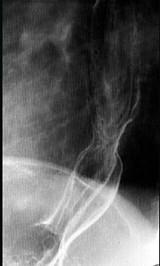

问题 女性,65岁,进行性吞咽困难半年,消瘦,钡餐检查如图,最佳的诊断是 ( )

选项 A.贲门失弛缓症 B.食管静脉曲张 C.食管鳞状(上皮)细胞癌 D.贲门癌 E.反流性食管炎

答案 C